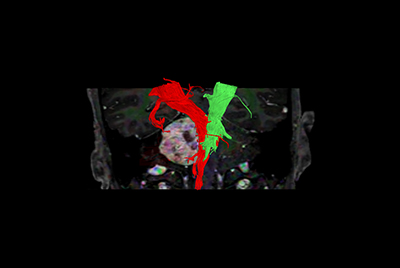

Pediatric brain with AVM

Brachial plexus tumor

Brachial Plexus with a hemangioma

Brachial Plexus lesion

Non-subtraction MR Angiography